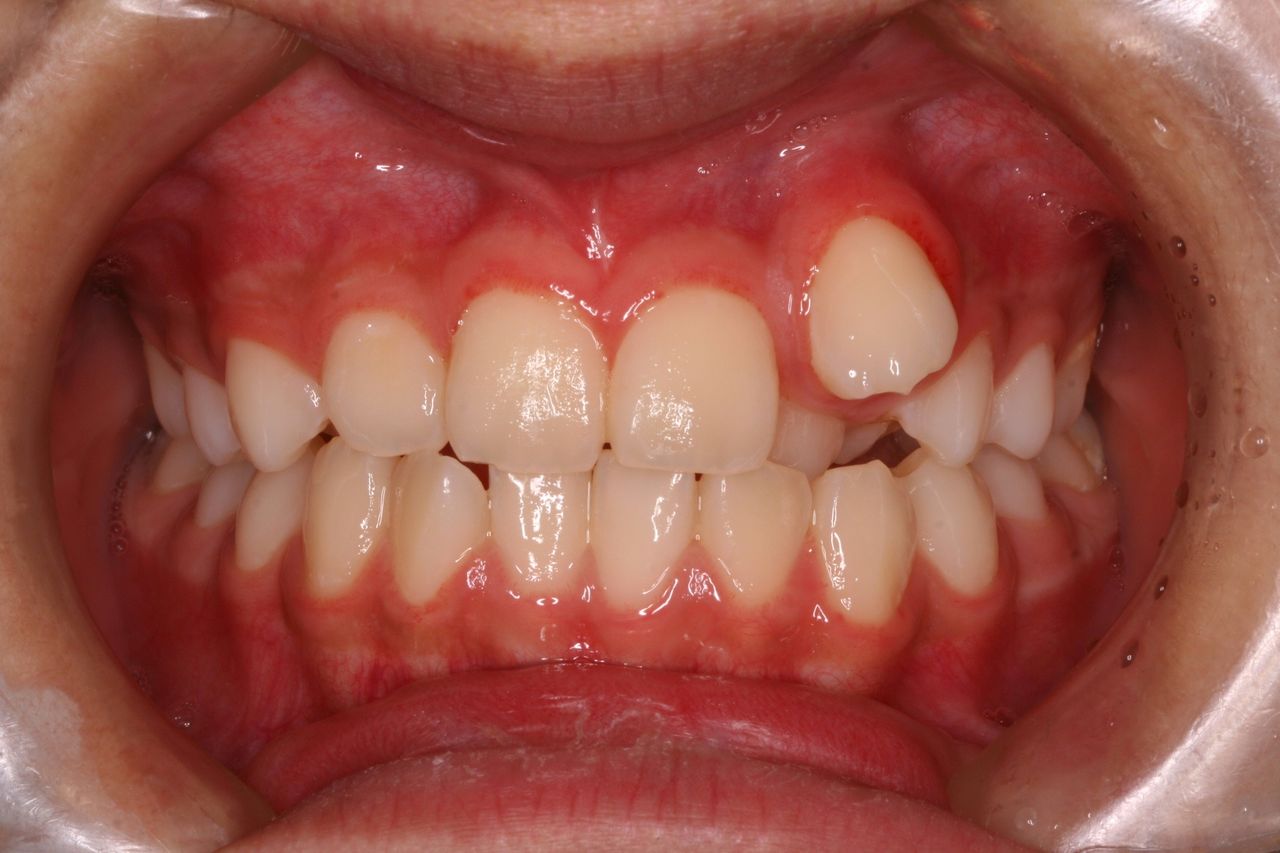

たとえばこのような状況の場合、犬歯はまったく機能しておりません。

これを抜歯して矯正治療をおこない、他の歯を100%機能させております。

正面からみると、普通のガタガタな歯並びですが、機能的には大変な状況です。

こんな具合です。

さきほどの患者さんの治療経過です。